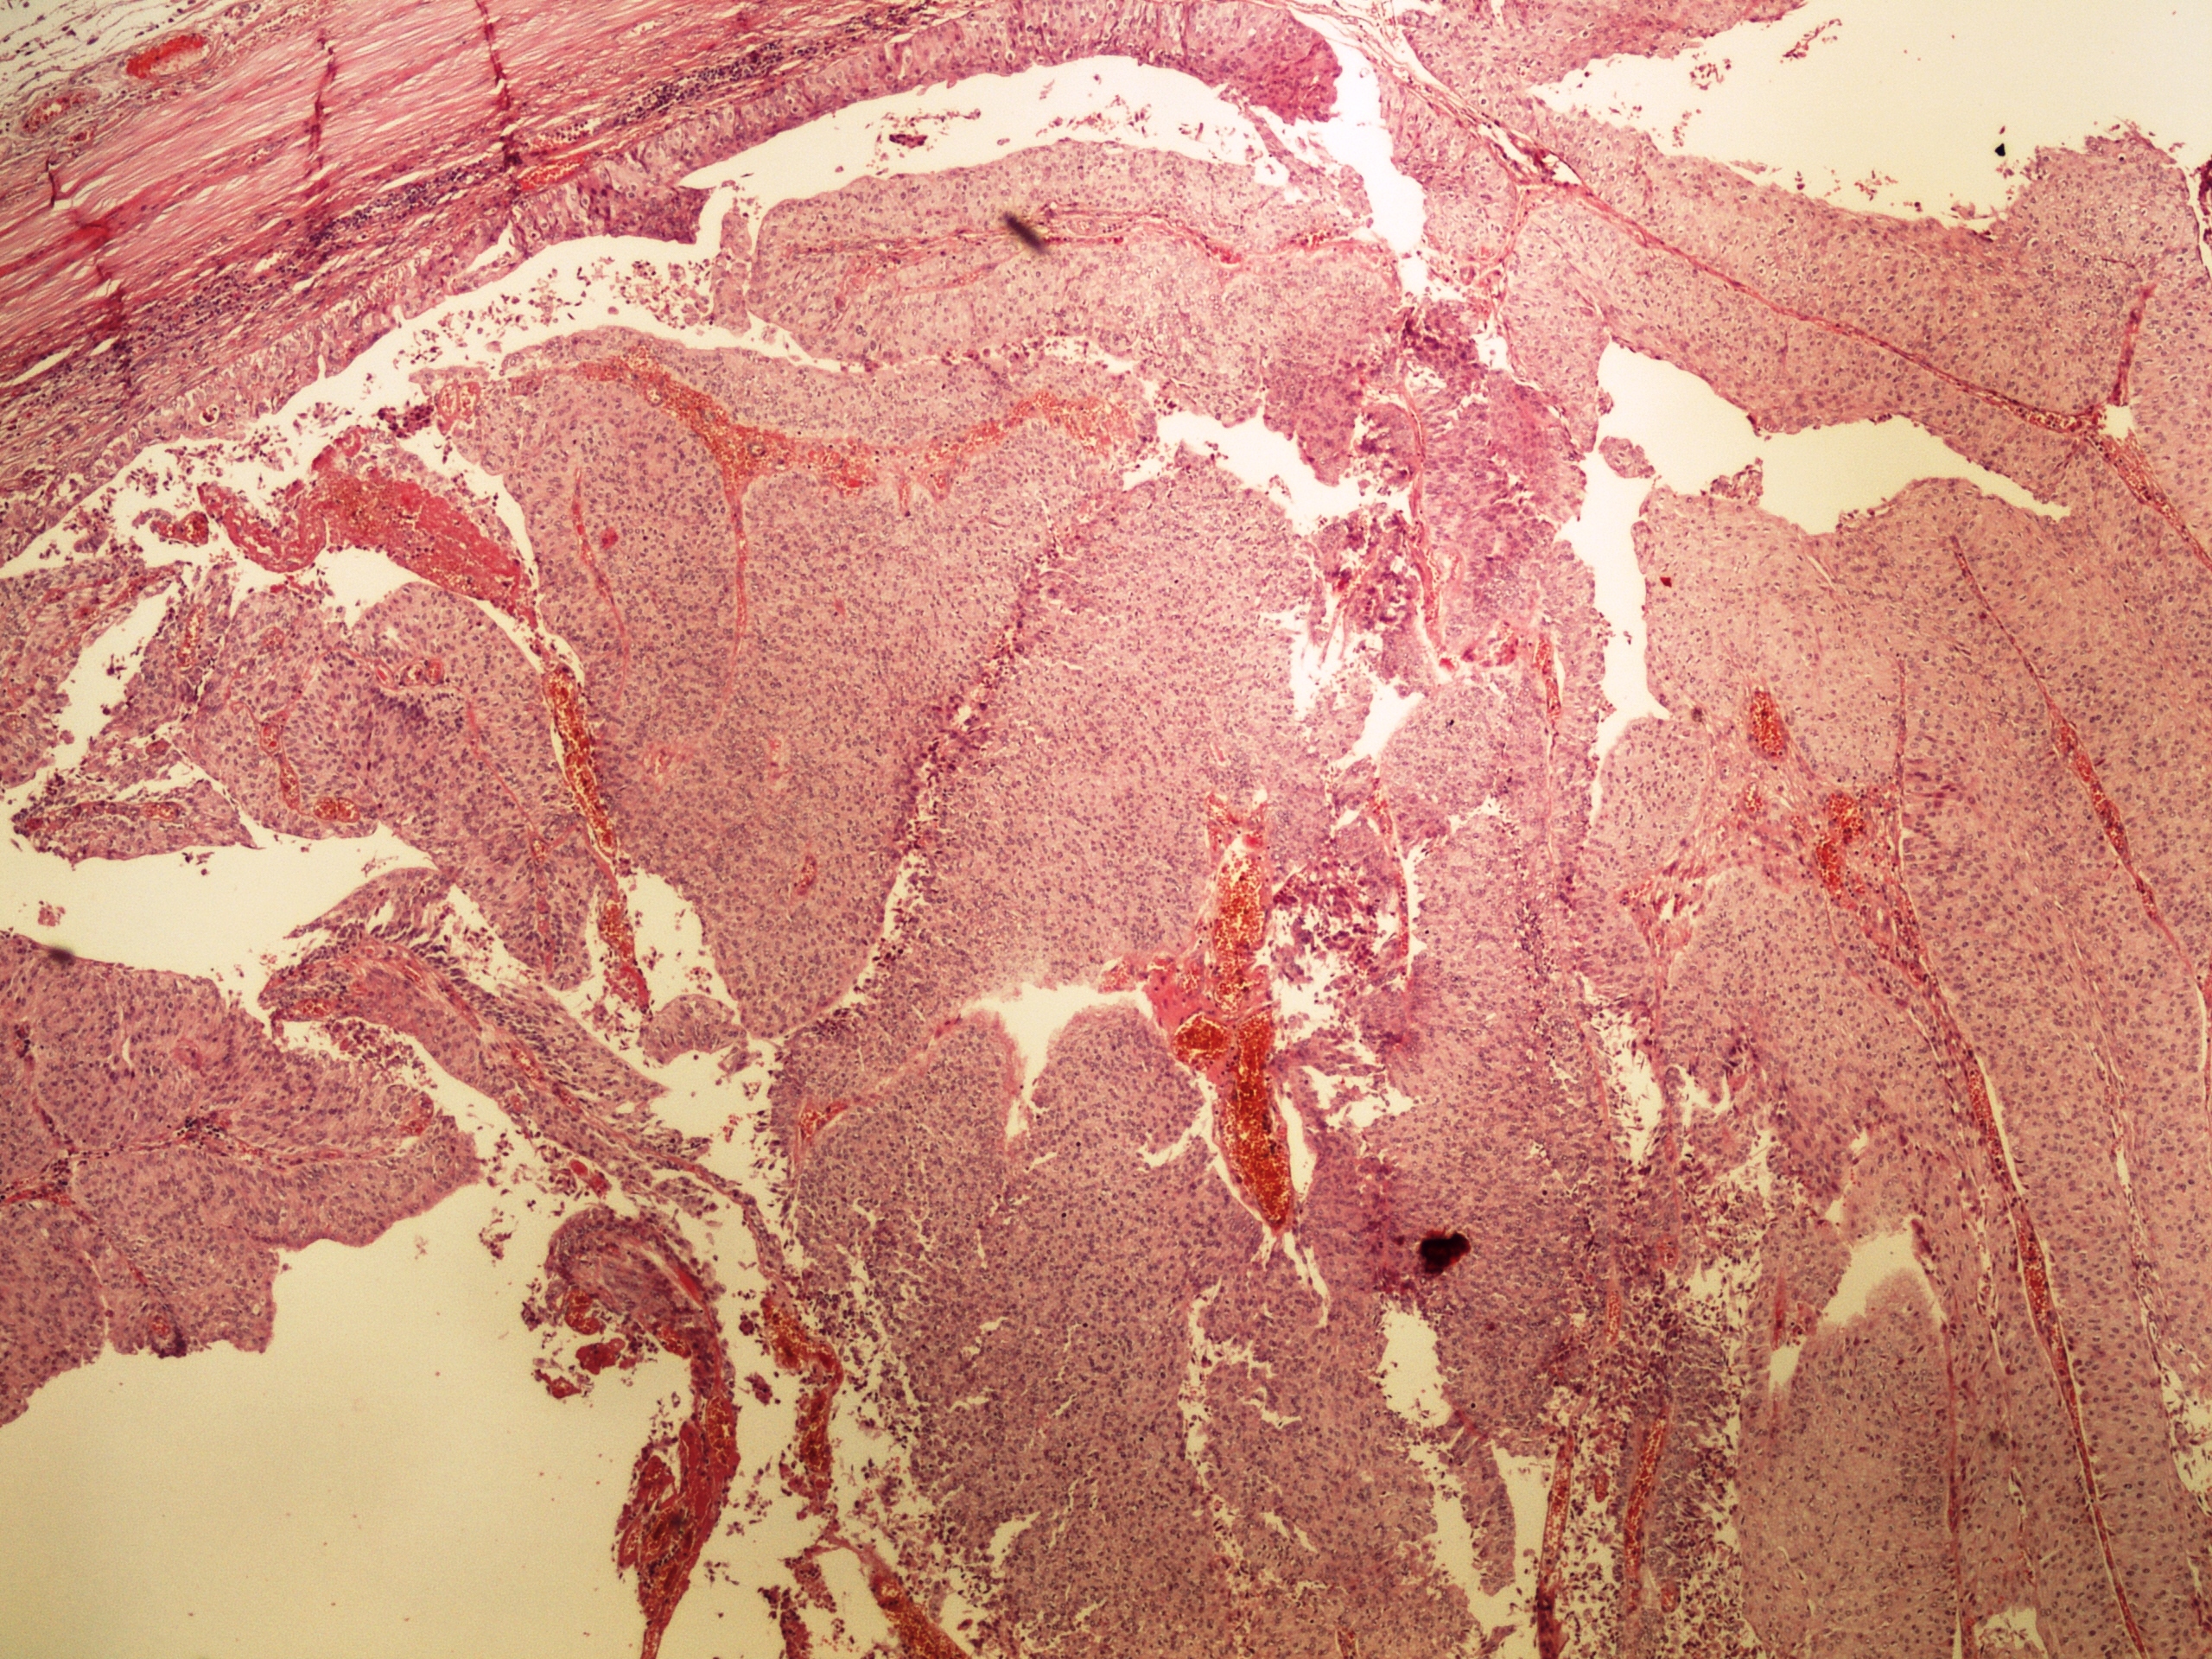

Preparát č.5 a č.6 - tubulární adenokarcinom

Struktury

- tumor

- invazivní čepy

- tubulární formace